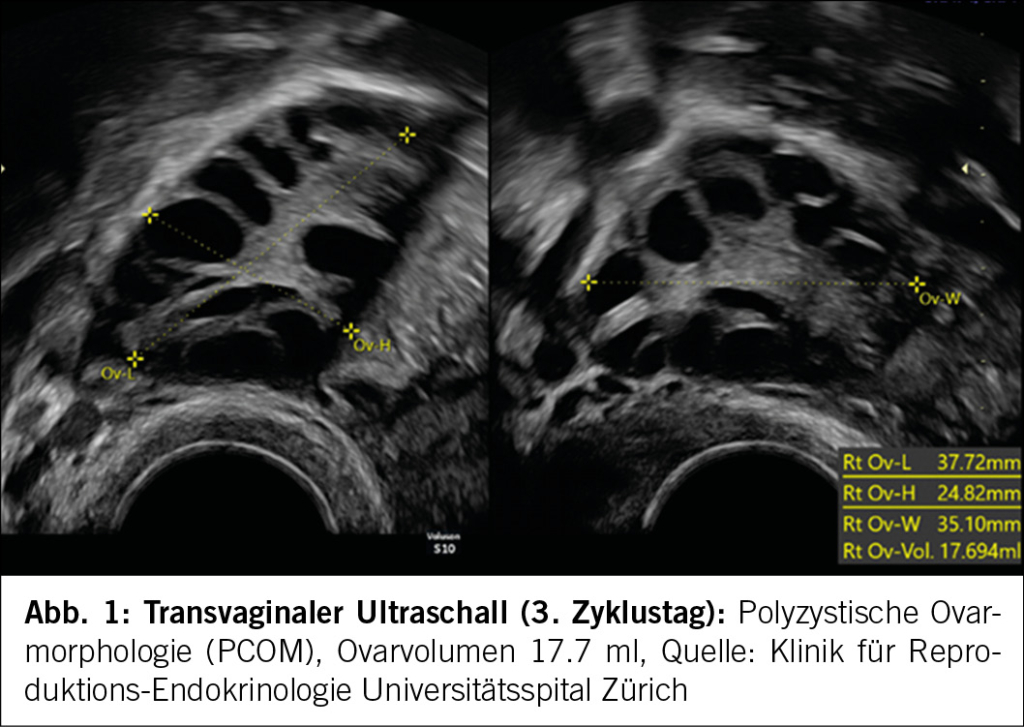

Namensgebend für das PCOS ist eine polyzystische Ovarmorphologie (PCOM) (Abb. 1). Die Ovarienbeurteilung sollte frühzyklisch (2.-5. Zyklustag) und ohne Nachweis eines dominanten Follikels, Corpus luteums oder einer Zyste erfolgen. Es muss zwischen dem transvaginalen und transabdominalen Ultraschall unterschieden werden (Tab. 1). Eine PCOM kommt bei Adoleszentinnen sehr häufig vor (9), sodass polyzystische Ovarien frühestens 8 Jahre nach der Menarche diagnostiziert werden dürfen. Bei Adoleszentinnen mit Zyklusstörungen und Hyperandrogenismus darf ohne Ultraschall und nach Ausschluss anderer Ursachen ein PCOS diagnostiziert werden.